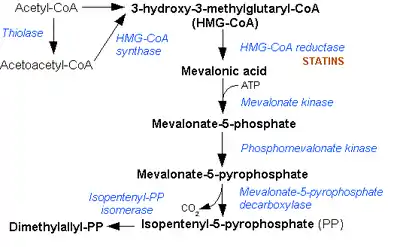

All animal cells manufacture cholesterol with relative production rates varying by cell type and organ function. About 20–25% of total daily cholesterol production occurs in the liver; other sites of higher synthesis rates include the intestines, adrenal glands, and reproductive organs. Synthesis within the body starts with one molecule of acetyl CoA and one molecule of acetoacetyl-CoA, which are dehydrated to form 3-hydroxy-3-methylglutaryl CoA (HMG-CoA). This molecule is then reduced to mevalonate by the enzyme HMG-CoA reductase. This step is the regulated, rate-limiting and irreversible step in cholesterol synthesis and is the site of action for the statin drugs (HMG-CoA reductase competitive inhibitors). Mevalonate is then converted to 3-isopentenyl pyrophosphate in three reactions that require ATP. This molecule is decarboxylated to isopentenyl pyrophosphate, which is a key metabolite for various biological reactions. Three molecules of isopentenyl pyrophosphate condense to form farnesyl pyrophosphate through the action of geranyl transferase. Two molecules of farnesyl pyrophosphate then condense to form squalene by the action of squalene synthase in the endoplasmic reticulum. Oxidosqualene cyclase then cyclizes squalene to form lanosterol. Finally, lanosterol is then converted to cholesterol. Konrad Bloch and Feodor Lynen shared the Nobel Prize in Physiology or Medicine in 1964 for their discoveries concerning the mechanism and regulation of cholesterol and fatty acid metabolism[4].

Mevalonic acid pathway Many organisms manufacture terpenoids through the HMG-CoA reductase pathway, the pathway that also produces cholesterol. The reactions take place in the cytosol. The pathway was discovered in the 1950s.

Mevalonate pathway and Statins

The mevalonate pathway or HMG-CoA reductase pathway or mevalonate-dependent (MAD) route or isoprenoid pathway, is an important cellular metabolic pathway present in all higher eukaryotes and many bacteria. It is important for the production of dimethylallyl pyrophosphate (DMAPP) and isopentenyl pyrophosphate (IPP), which serve as the basis for the biosynthesis of molecules used in processes as diverse as terpenoid synthesis, protein prenylation, cell membrane maintenance, hormones, protein anchoring, and N-glycosylation. It is also a part of steroid biosynthesis[24].

Several key enzymes can be activated through DNA transcription al regulation on activation of SREBP (sterol regulatory element-binding protein-1 and -2). This intracellular sensor detects low cholesterol levels and stimulates endogenous production by the HMG-CoA reductase pathway, as well as increasing lipoprotein uptake by up-regulating the LDL-receptor. Regulation of this pathway is also achieved by controlling the rate of translation of the mRNA, degradation of reductase and phosphorylation.

| Reaction | Diagram | Enzyme |

| Acetyl-CoA (citric acid cycle) undergoes condensation with another acetyl-CoA subunit via Acetyl-CoA Transferase to form acetoacetyl-CoA | thiolase | |

| Acetyl-CoA condenses with acetoacetyl-CoA to form 3-hydroxy-3-methylglutaryl-CoA (HMG-CoA). | HMG-CoA synthase | |

| HMG-CoA is reduced to mevalonate by NADPH. This reaction occurs in the cytosol. It is the rate limiting step in cholesterol synthesis, which is why the enzyme catalyzing the reaction is a target of statins. | HMG-CoA reductase | |

| Mevalonate to 5-phosphomevalonate. |  | mevalonate kinase |

| 5-phosphomevalonate to 5-pyrophosphomevalonate. | phosphomevalonate kinase | |

| Mevalonate-5-pyrophosphate to 3-isopentenyl pyrophosphate (IPP) (see also HIDS). |  | mevalonate-5-pyrophosphate decarboxylase |

| 3-isopentenyl pyrophosphate is isomerized to dimethylallyl pyrophosphate. |  | isopentenyl pyrophosphate isomerase |

In 1971, Akira Endo, a Japanese biochemist working for the drug company Sankyo, began the search for a cholesterol-lowering drug. Research had already shown that cholesterol is mostly manufactured by the body in the liver, using an enzyme known as HMG-CoA reductase. Endo and his team reasoned that certain microorganisms may produce inhibitors of the enzyme to defend themselves against other organisms, as mevalonate is a precursor of many substances required by organisms for the maintenance of their cell wall (ergosterol) or cytoskeleton (isoprenoids). The first agent they identified was mevastatin (ML-236B), a molecule produced by the fungus Penicillium citrinum. Journalist John Simons writes in Fortune magazine that word of the discovery spread quickly through the medical community, as did rumors linking the statin to tumors, muscle deterioration, and sometimes death in laboratory dogs. Several drug companies were put off by these reports, but P. Roy Vagelos, the chief scientist and later CEO of Merck & Co, showed an interest, and made several trips to Japan starting in 1975. By 1978, Merck had isolated lovastatin (mevinolin, MK803) from the fungus Aspergillus terreus, first marketed in 1987 as Mevacor. A link between cholesterol and cardiovascular disease, known as the lipid hypothesis, had already been suggested. Cholesterol is the main constituent of atheroma, the fatty lumps in the wall of arteries that occur in atherosclerosis and, when ruptured, cause the vast majority of heart attacks. Treatment consisted mainly of dietary measures such as a low-fat diet, and poorly tolerated medicines such as clofibrate, cholestyramine and nicotinic acid. Cholesterol researcher Daniel Steinberg writes that while the Coronary Primary Prevention Trial of 1984 demonstrated that cholesterol lowering could significantly reduce the risk of heart attacks and angina, physicians, including cardiologists, remained largely unconvinced. To market statins effectively, Merck had to convince the public about the dangers of high cholesterol, and doctors that statins were safe and would extend lives. As a result of public campaigns, people became familiar with their cholesterol numbers and the difference between "good" and "bad" cholesterol, and rival pharmaceutical companies began producing their own statins, such as pravastatin (Pravachol), manufactured by Sankyo and Bristol-Myers Squibb. In April 1994, the results of a Merck-sponsored study, the Scandinavian Simvastatin Survival Study or "4S", were announced. Researchers tested simvastatin, later sold by Merck as Zocor, on 4,444 patients with high cholesterol and heart disease. After five years, the study concluded that patients saw a 35-percent reduction in their cholesterol, and their chances of dying of a heart attack were reduced by 42 percent. In 1995, Zocor and Mevacor both made Merck over US$1 billion. Endo was awarded the 2006 Japan Prize, and the Lasker-DeBakey Clinical Medical Research Award in 2008. Statins act by competitively inhibiting HMG-CoA reductase, the first committed enzyme of the HMG-CoA reductase pathway. Because statins are similar to HMG-CoA on a molecular level they take the place of HMG-CoA in the enzyme and reduce the rate by which it is able to produce mevalonate, the next molecule in the cascade that eventually produces cholesterol, as well as a number of other compounds. This ultimately reduces cholesterol via several mechanisms[25].

Mode of action of Statins

Inhibiting cholesterol synthesis By inhibiting HMG-CoA reductase, statins block the pathway for synthesizing cholesterol in the liver. This is significant because most circulating cholesterol comes from internal manufacture rather than the diet. When the liver can no longer produce cholesterol, levels of cholesterol in the blood will fall. Cholesterol synthesis appears to occur mostly at night, so statins with short half-lives are usually taken at night to maximize their effect. Studies have shown greater LDL and total cholesterol reductions in the short-acting simvastatin taken at night rather than the morning, but have shown no difference in the long-acting atorvastatin.

Increasing LDL uptake Liver cells sense the reduced levels of liver cholesterol and seek to compensate by synthesizing LDL receptors to draw cholesterol out of the circulation. This is accomplished via protease enzymes that cleave a protein called "membrane-bound sterol regulatory element binding protein", which migrates to the nucleus and causes increased production of various other proteins and enzymes, including the LDL receptor. The LDL receptor then relocates to the liver cell membrane and binds to passing LDL and VLDL particles (the "bad cholesterol" linked to disease). LDL and VLDL are drawn out of circulation into the liver where the cholesterol is reprocessed into bile salts. These are excreted, and subsequently recycled mostly by an internal bile salt circulation.